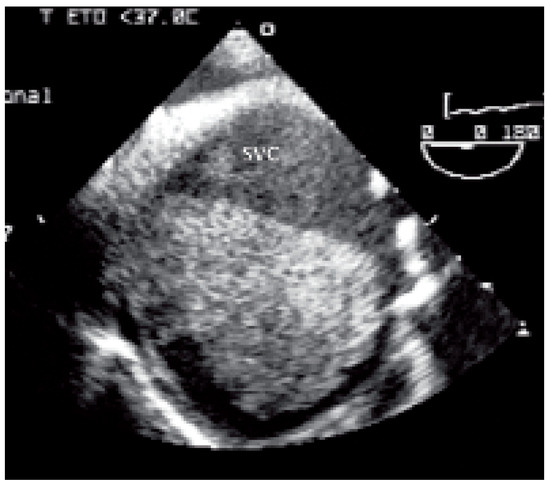

Case report